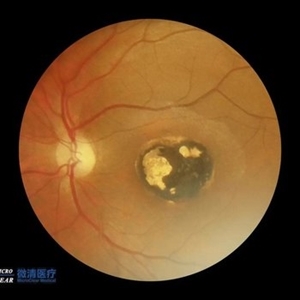

Congenital Toxoplasmosis

Congenital Toxoplasmosis

Jul 22 2017 by Akif Erol

Color fundus photograph of the left eye of an 18-year-old girl with decreased vision due to a large chorioretinal scar involving the macula. The lesion is typical for a congenital ocular toxoplasmosis

Photographer: Mehmet Akif Erol, Afyon Kocatepe University Ophthalmology Clinic

Condition/keywords: color fundus photograph, congenital toxoplasmosis